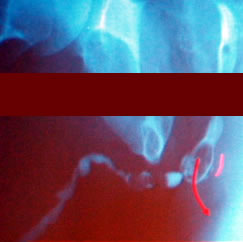

"Новые технологии в лечении стриктур уретры"

Распространенное

заболевание

Повторные неудачные

попытки восстановления

Окончательная

промежностная уретростомия